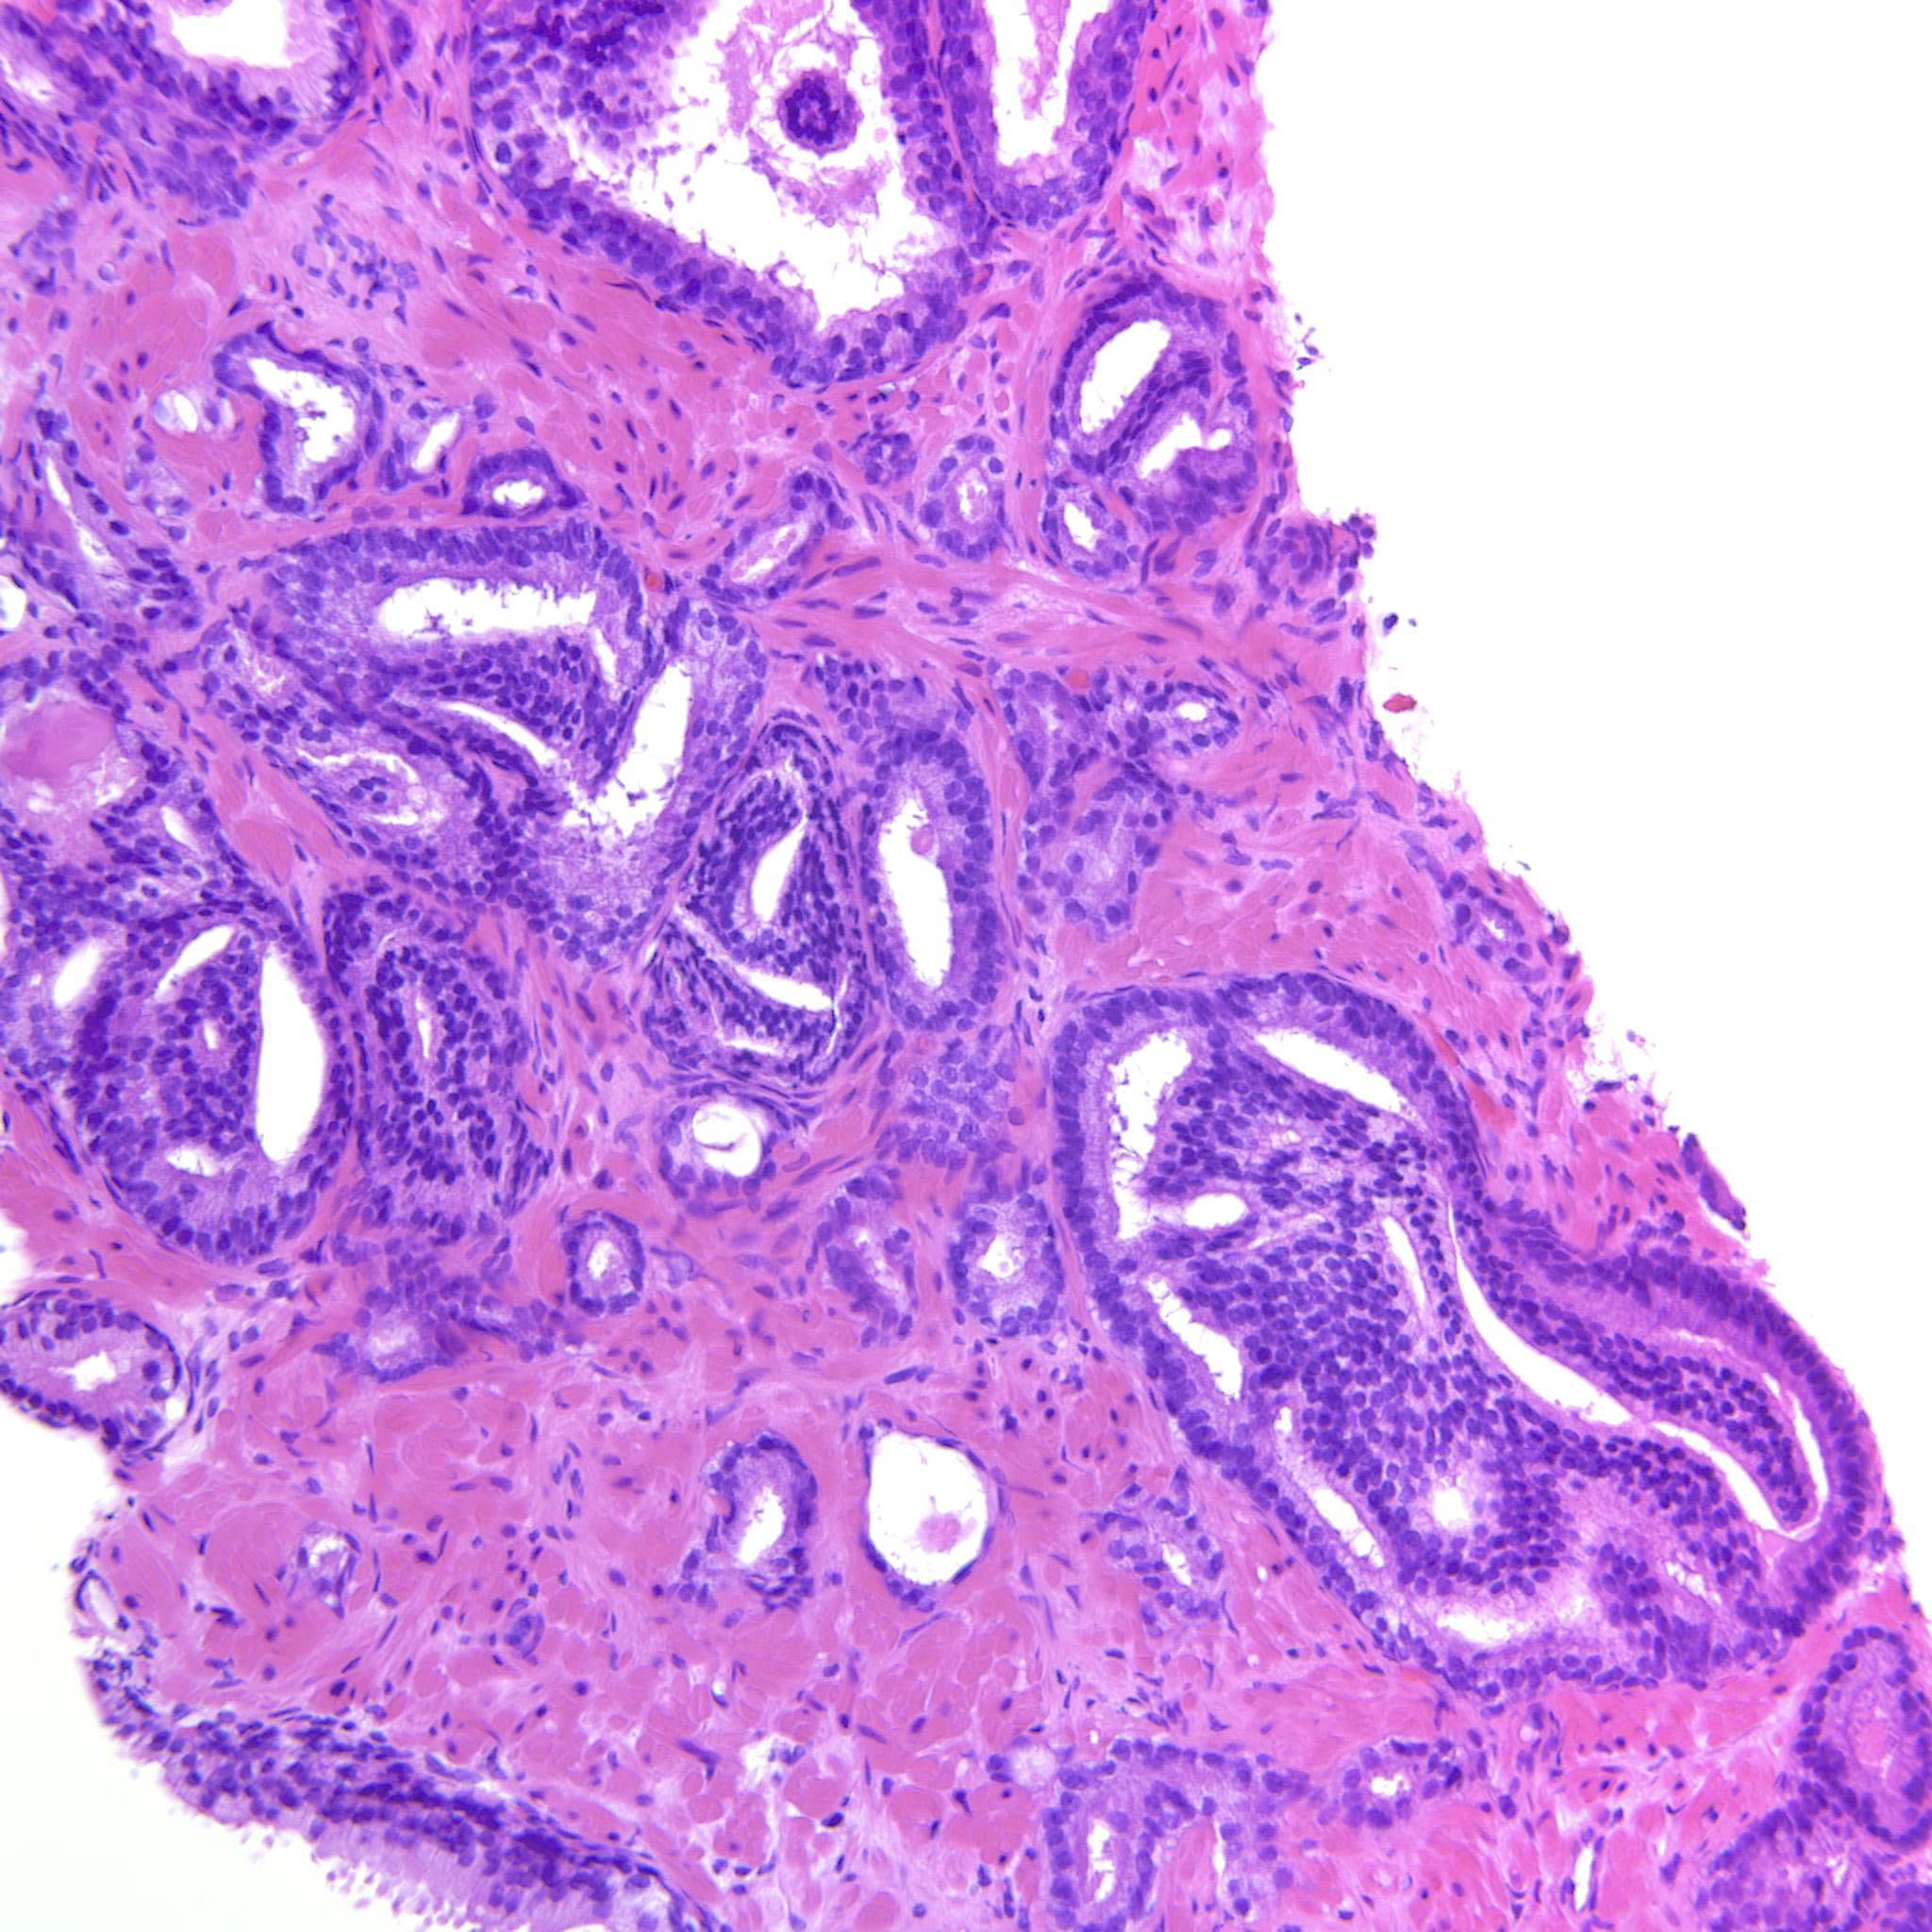

Consensus grade: GS 3+4=7 (ISUP 2)

Case description (by case creator):

Mostly GP3 but there are also a few cribriform glands.